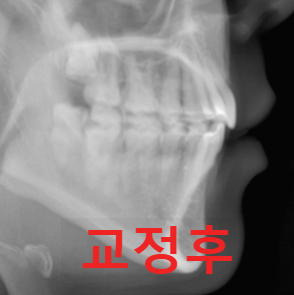

2. 두개골(머리뼈) 방사선 촬영

3. 치아 방사선 촬영